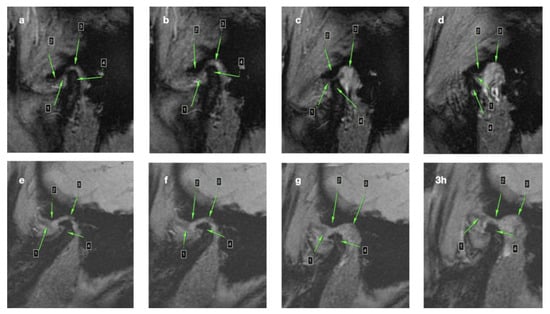

3.2. Cone-Beam Computed Tomography (CBCT)